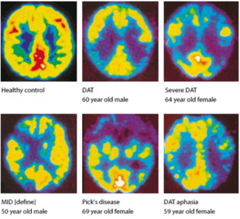

What is the PET scan finding representative of Alzheimer’s dementia?

Pick’s disease

How do patients with frontotemporal dementia usually presnet? What type of histological findings are seen upon autopsy?